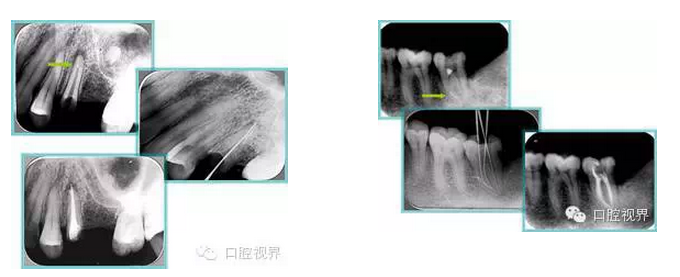

7. 器械折斷

右圖及下圖為器械折斷的 X 線片。箭頭處示折斷器械。

解決方法: ( 1 )取出。 ( 2 )通過。 ( 3 )重新確定工作長度,充填。 ( 4 )根尖手術(shù)。

器械折斷可以不用取出,取出的原因多是患者心理因素。留在里面的器械關(guān)鍵是進行消毒,預(yù)防性使用抗感染藥物,預(yù)防感染。